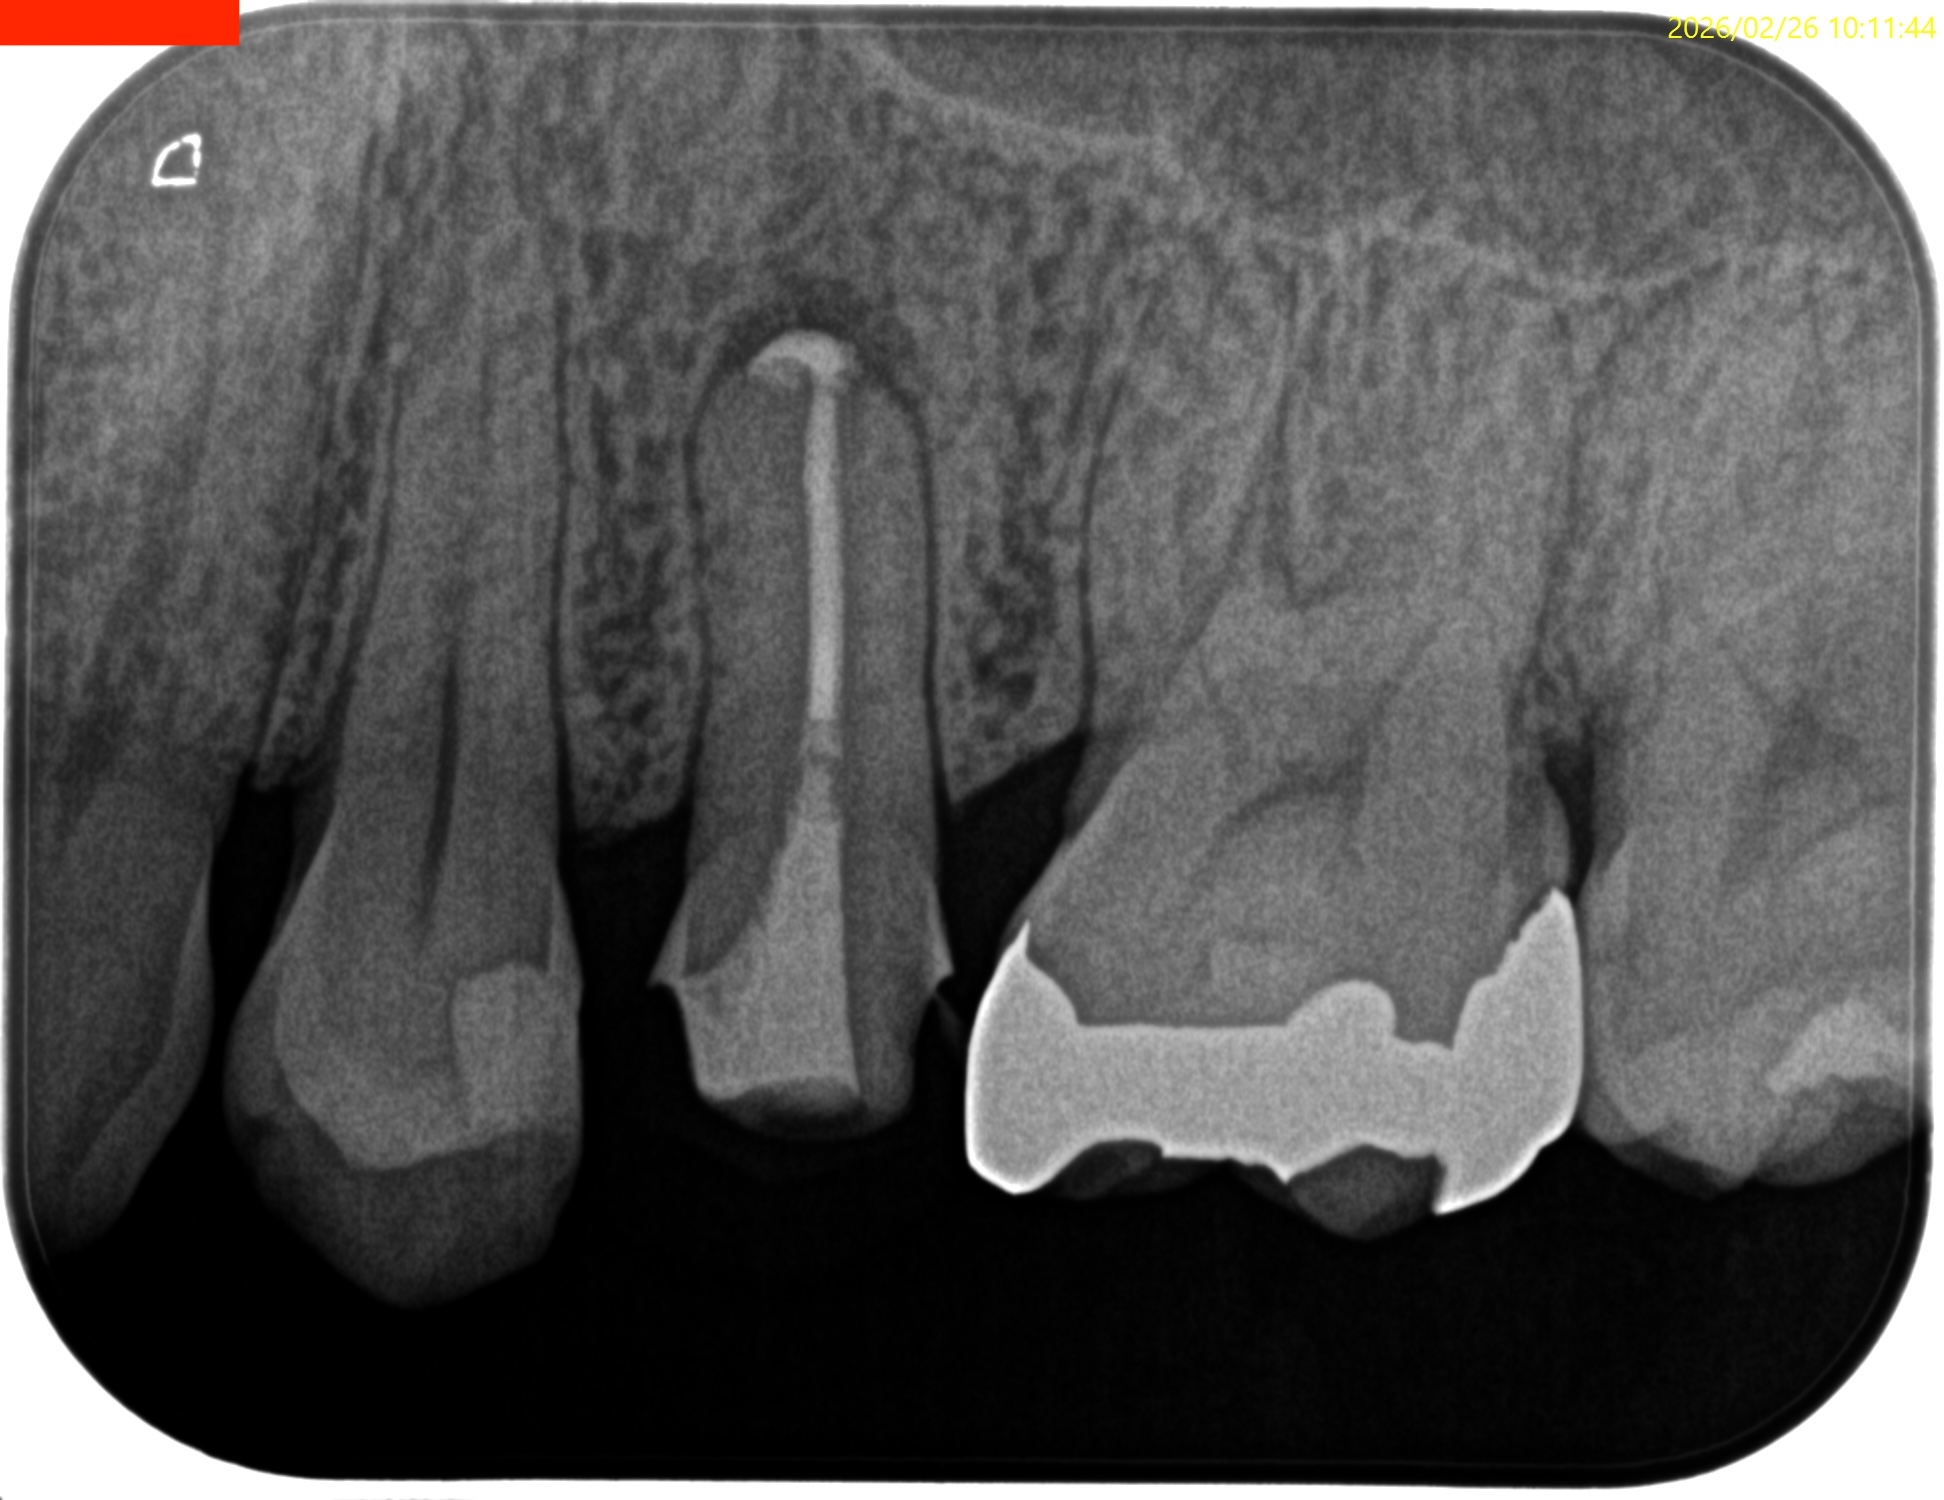

#13 RCT(2025.2.4)

合流地点を確認し以下のように根管形成して

術後にPA, CBCTを撮影した。

B

P